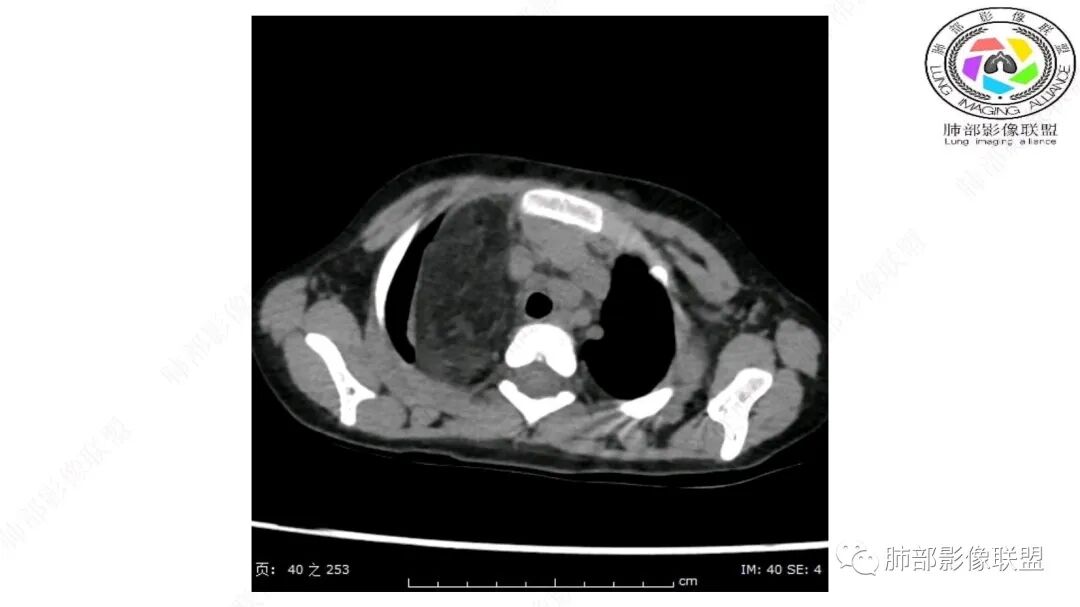

定位:肺内?尖段气管未见明显显示,腔静脉受压向右推移?病灶内可见前段动脉穿行,脂肪密度为主。

肿块起源于右上气管分叉处?强化动脉血管最后汇入右肺动脉上干。

跨肺门,包绕肺血管分支,邻近肺组织受压肺不张。

可以看到造影剂进入的丛状结构

密度不均,非纯脂肪成分。斑片状密度略高区域有轻度填充式强化。

婴幼儿,病变较大,跨肺门,分叶,富含纤维或黏液、含成熟脂肪,破坏力弱或无,浸润性生长模式不明显,未见远处转移。

病灶属于交界区,主体位于肺内,占位效应明显,前方突入胸壁,胸腺受压变形,胸膜显示欠清楚;病灶包绕上叶肺动脉;似乎有体动脉供血。符合肺内的点:包绕上叶肺动脉分支;符合纵隔的点:前方似乎突入胸壁,与胸腺关系比较密切,但是与上腔静脉的关系提示病灶不支持纵隔来源,前纵隔的常规会将上腔静脉受压后移、外移,这是不符合的。

内部血管明显,部分病灶密度增高,单纯脂肪瘤不支持。可惜的是:没有提供CT值:是否强化?如果强化,警惕恶性;胸腺肯定不符合,胸腺会将上腔静脉朝后推移。